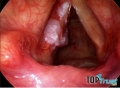

Căn Bệnh Ung Thư